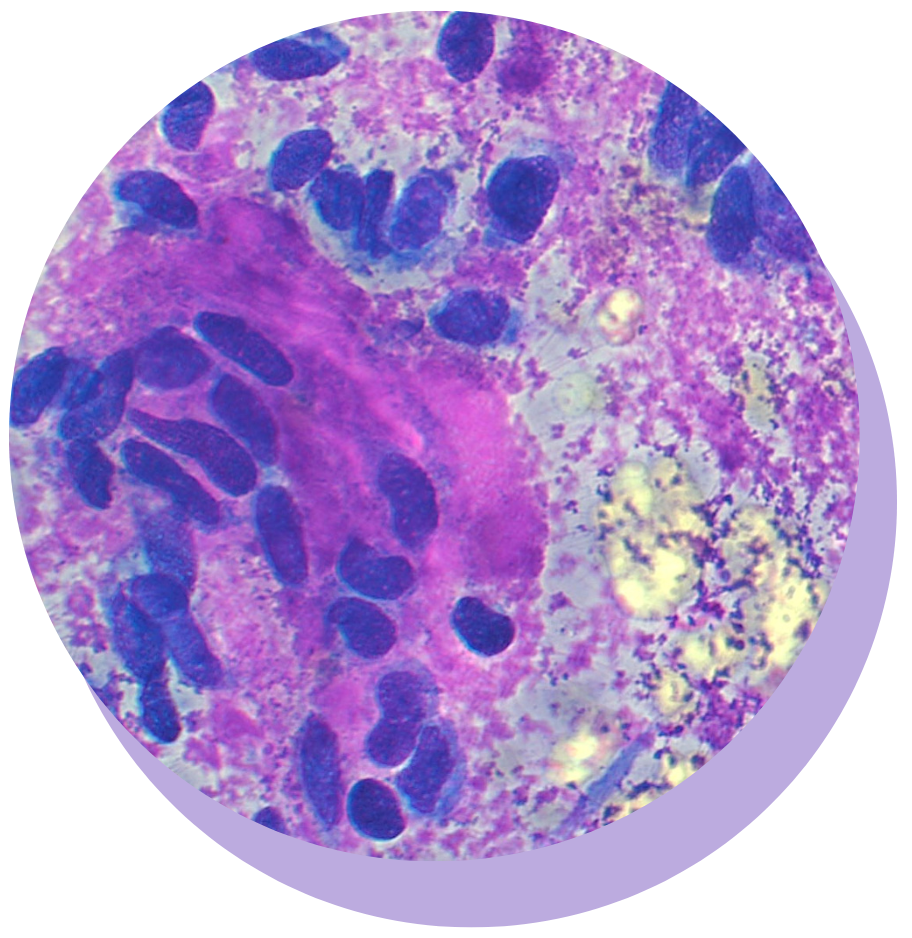

MASTERING CYTOLOGY: SKIN AND SUBCUTIS

Boost your confidence and skills in interpretation of fine-needle aspirate (FNA) cytology from masses/lesions in the skin and subcutis.